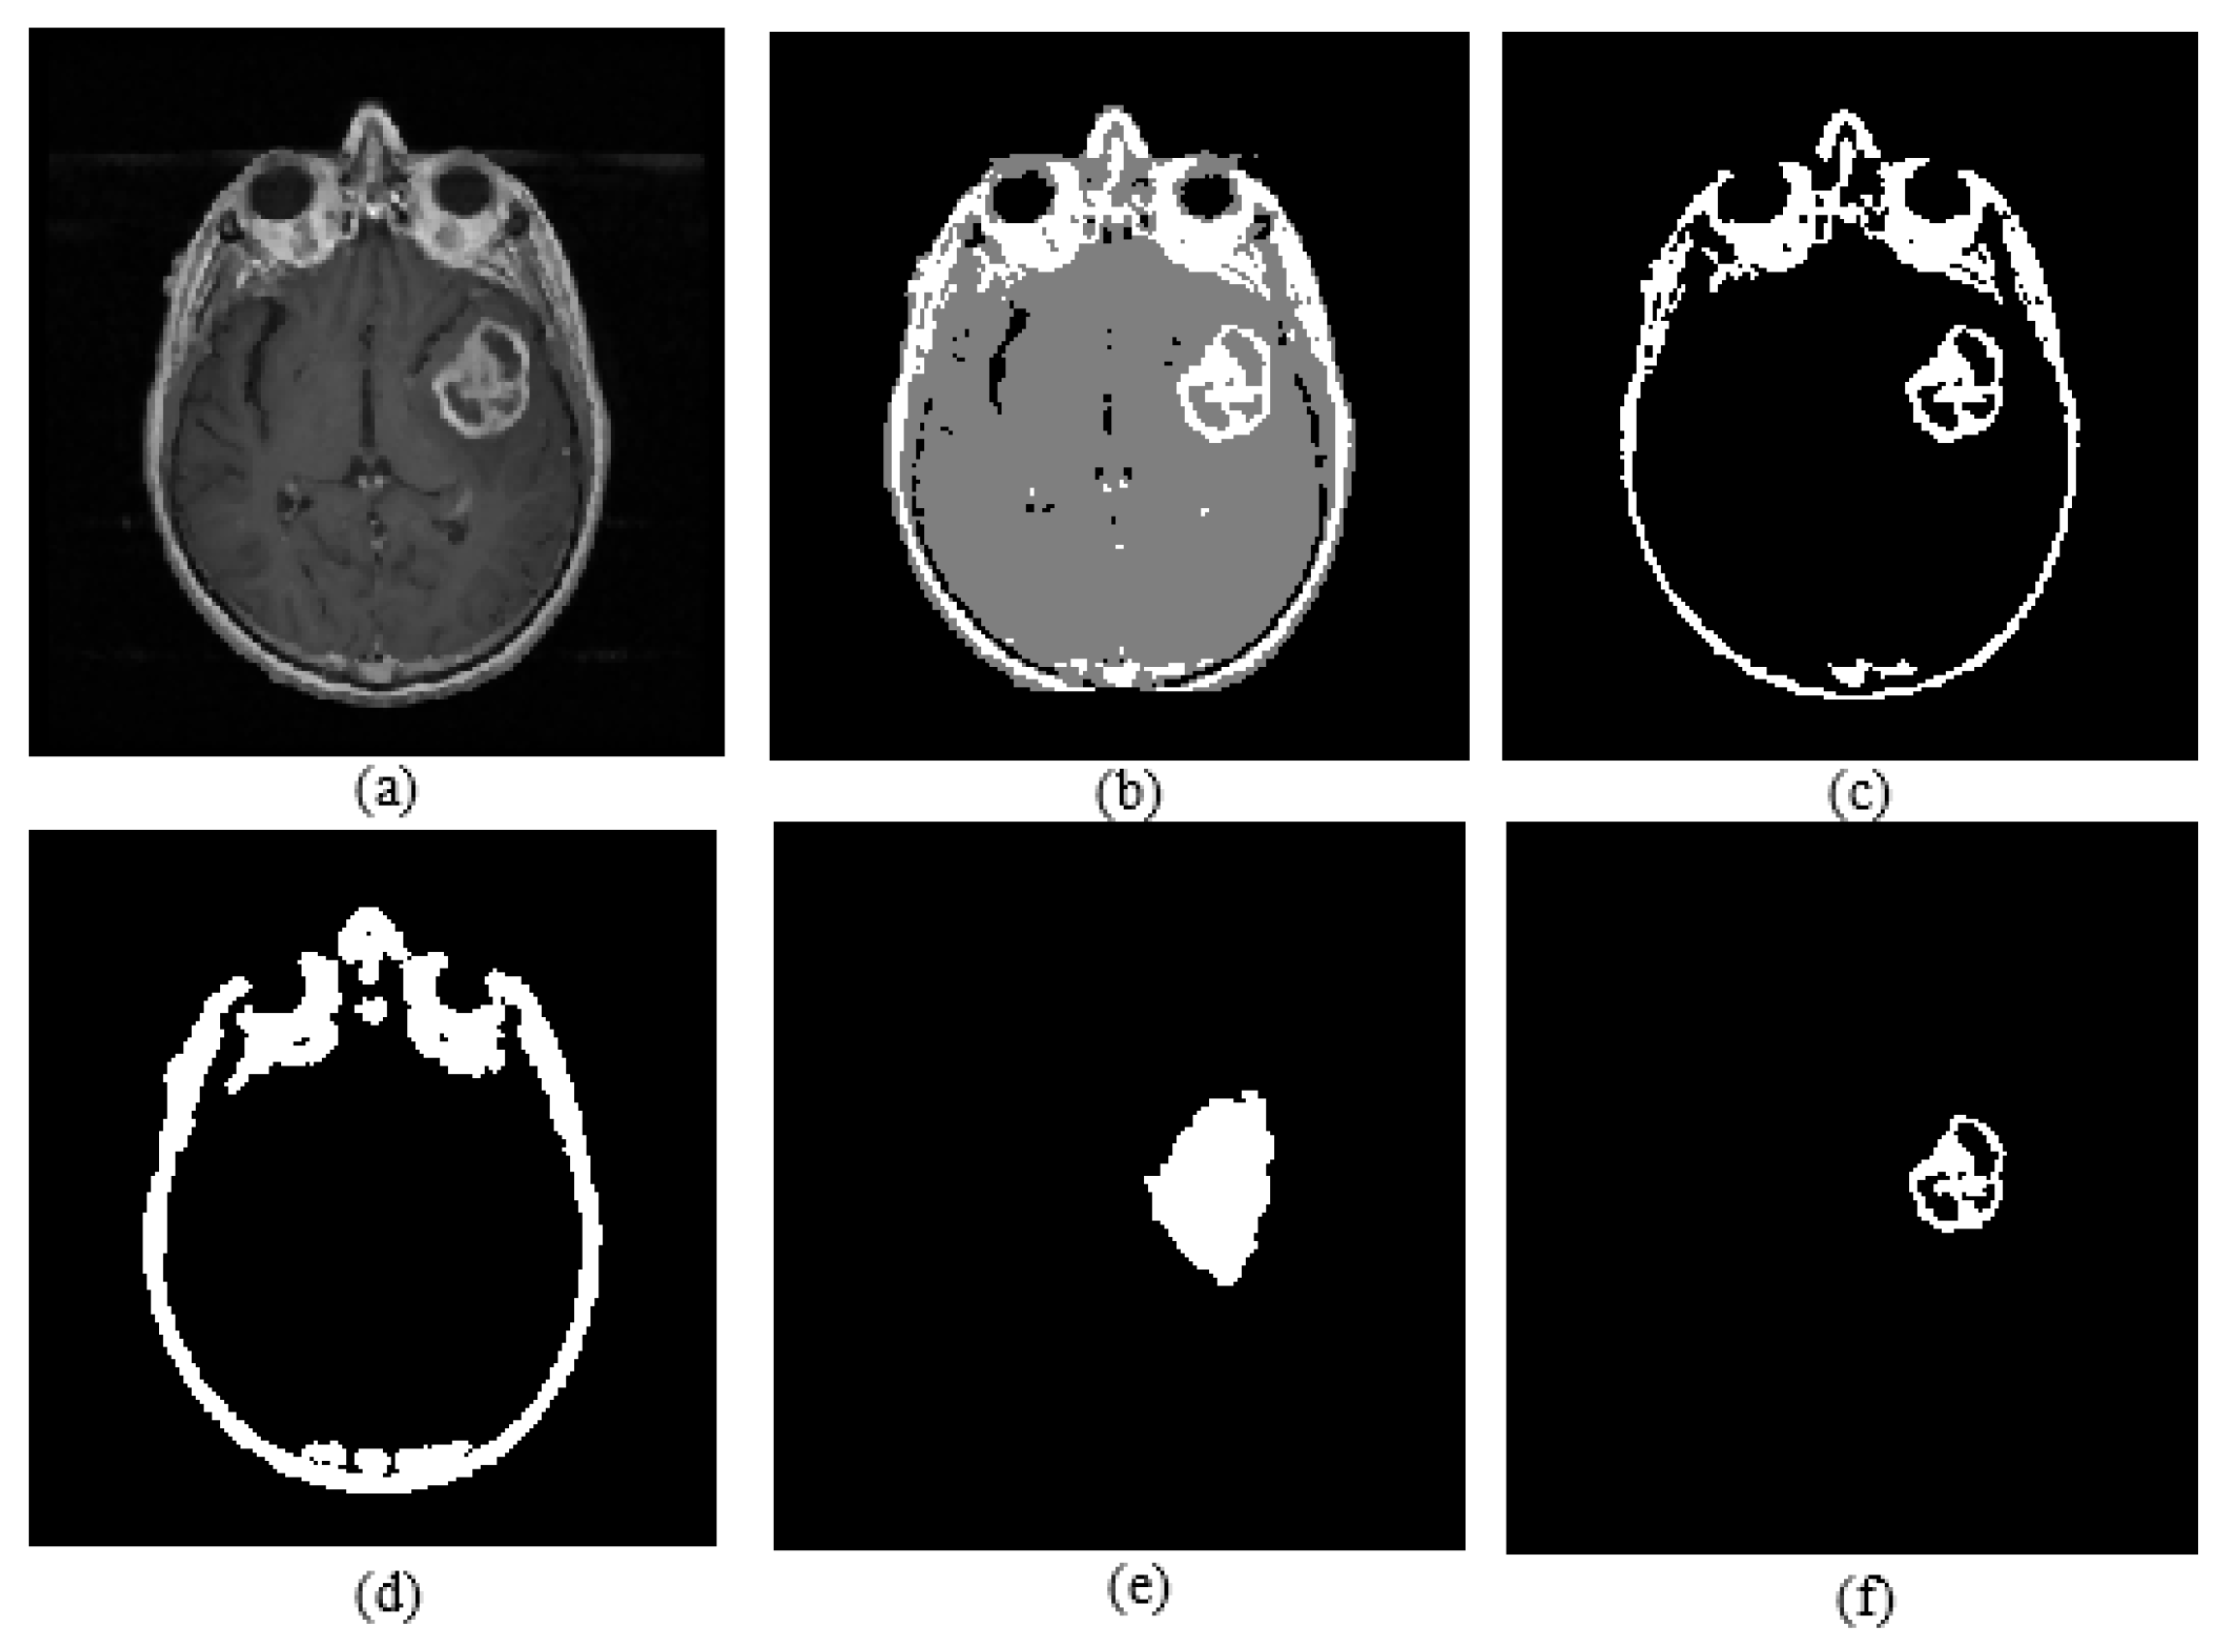

Active core segmentation and the volume estimation stage involve masking and FCM clustering operations, as outlined in Figure 11. The T1C image is converted to a binary image via FCM and a morphological opening operation (Figure 12c), and then skull stripping and whole tumor masks (Figure 12d,e) are applied on this image to obtain the enhancing/active core (Figure 12f). To obtain the necrotic/cystic core, a morphological closing operation is applied on the active core region (Figure 13c), then the active core is subtracted from this image (Figure 13d).

Figure 12.

(a) T1C image; (b) fuzzy c-means clustering result; (c) binary image including active core; (d) skull stripping mask; (e) whole tumor mask; (f) enhancing tumor.